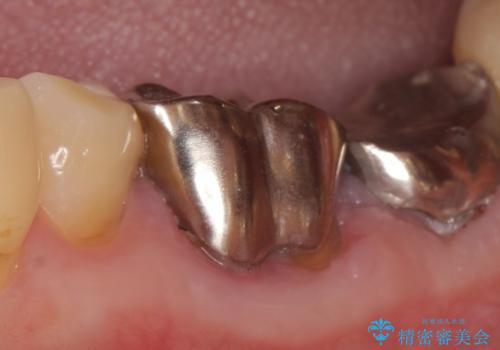

- 左下の銀歯が外れたので診て欲しいといらっしゃった方の症例です。

他院にて再装着したが不安なので、根管治療からやり直したいとのことでした。